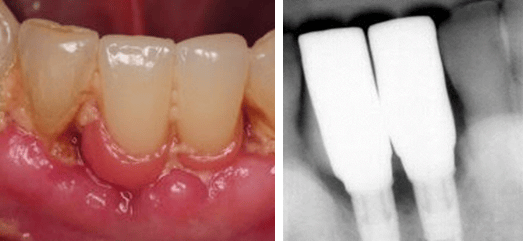

Case Example 1: Two-unit bridge supported by two implants

The first case example is of a two-unit implant-supported bridge in place of missing teeth numbers 24-25. There is obvious moderate to heavy plaque and food accumulation with soft and hard tissue inflammation. The implant crowns being fused together with submucosal restorative margins limits access for personal oral hygiene in all embrasure spaces, especially between 24-25. The design of the restoration also created additional spaces, especially evident where the bridge meets adjacent teeth #23 and #26.

The pink acrylic in place of soft tissue is generally convex, contributing to a bulky restorative design and a non-maintainable environment. Although many factors need to be considered as contributing to the problem, perhaps the restorative doctor could have avoided some of these complications with the recommendation of two single implant crowns instead fusing the two together.